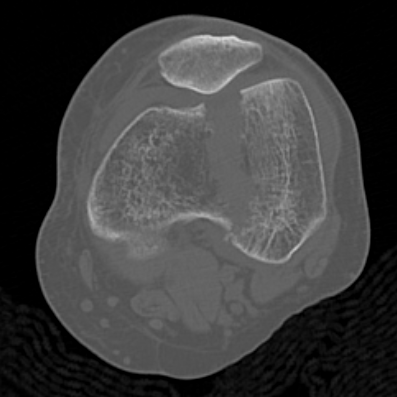

Type C: Complete articular

Xray / CT